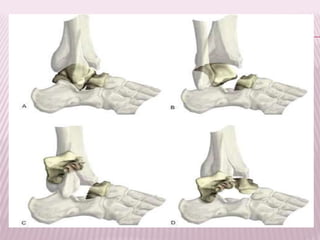

ASTRAGALO

 Cabeza

 Cuello

 Cola

Su incidencia oscila entre el 0,1% y el

0,85% de todas las fracturas.

Representan el 50% de las fracturas, mecanismo:

caída desde cierta altura con pie en flexión

dorsal.

Clasificación Hawkins:

I. Sin desplazamiento, alineación

normal de la articulación

subastragalina

II. Desplazada y asociada con

subluxación o luxación de la

articulación subastragalina

III. Desplazada y asociada con

luxación completa de la articulación

subastragalina como

tibioastragalina.

TRATAMIENTO

 Debe dirigirse a obtener la reducción para evitar problemas

de irrigación (necrosis).

 Tipo I. Inmovilización con bota enyesada.

 Tipo II. Tratar de reducir la luxación subastragalina con

movimiento de inversión o de eversión (osteosíntesis).

 Tipo III. Se intenta por reducción cerrada sino reducción

quirúrgica.